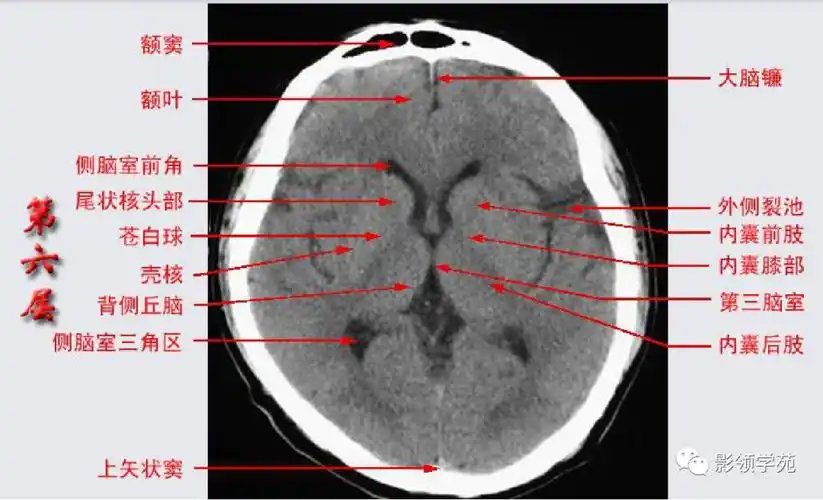

头部ct影像解剖